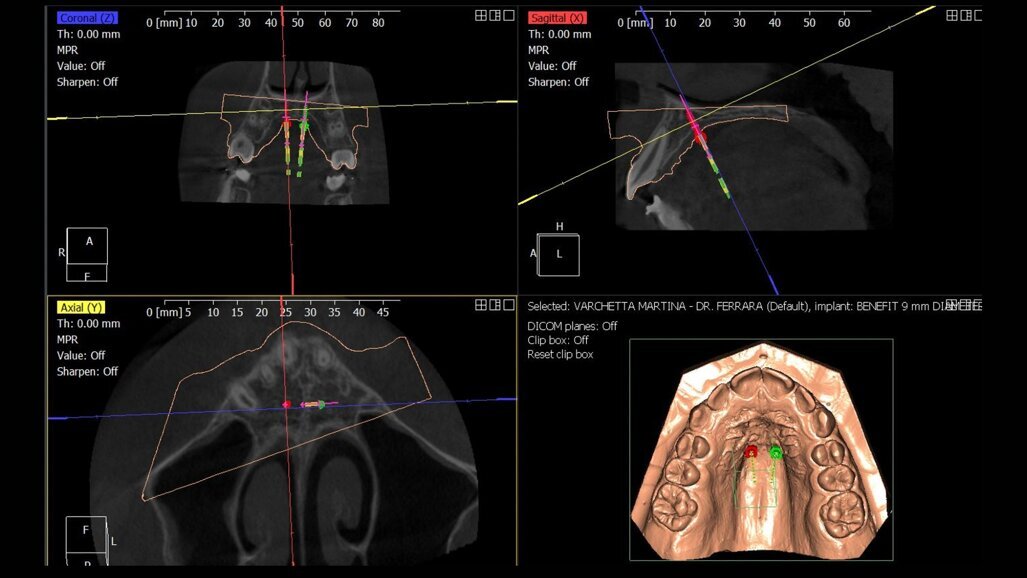

Fig. 4_Progettazione digitale mediante protocollo Easy Driver della posizione delle miniviti ortodontiche. Mediante il software è possibile programmare sito di inserimento, profondità è inclinazione dei TADs.

In questo stadio la fusione della sutura è già avvenuta parzialmente o totalmente, ed è quindi stata eseguito una MARPE. È stata progettata una dima CAD/CAM, mediante protocollo Easy Driver5. La CBCT è stata sovrapposta alla scansione digitale STL (standard triangulation language) dell’arcata dentale superiore, per valutare con estrema precisione il sito più adatto di inserimento, la lunghezza e il diametro delle viti, rispettando la profondità della volta palatina, e l’inclinazione di inserimento delle viti (Fig. 4).